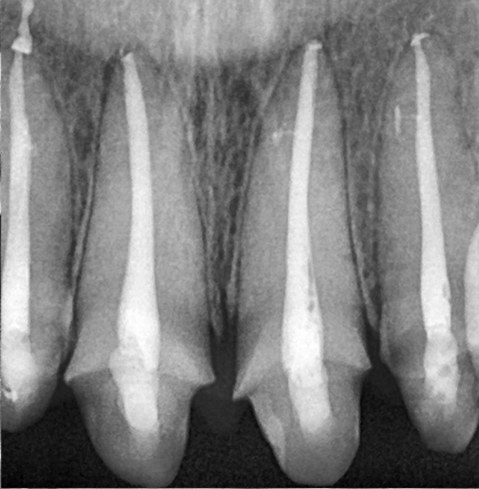

A panoramic X-ray was taken

to perform a detailed check,

and an overall treatment plan was established.

Because the front teeth are also an area that is visually noticeable,

the plan was carefully considered.